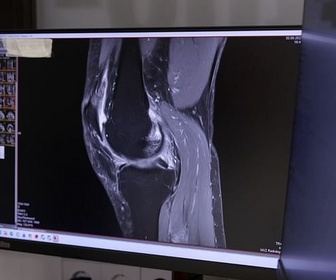

L'arthrose est une maladie douloureuse qui touche des millions d'adultes. On ne peut pas encore la guérir, mais elle pourrait être évitée dans de nombreux cas. Elle est souvent provoquée par de petites lésions du cartilage qui peuvent désormais être guéries en stimulant les capacités d'auto-guérison du corps.